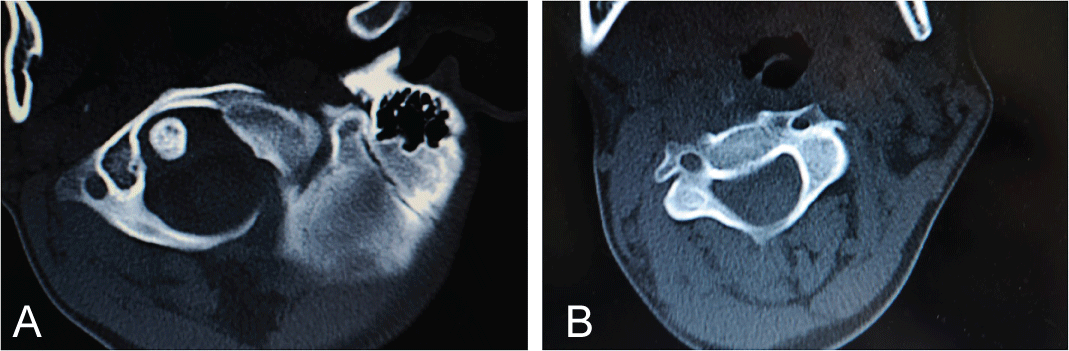

This patient study was approved by the Ethics Committee and was conducted following completion of the corresponding informed consent. A 10-year-old male patient in 2008 had consulted for a torticollis deformity that had originated during early childhood. This delay in first diagnosis is because patient is inmigrant and without diagnosis or previous treatment. Patient had classical deformities of torticollis: Shortening of SCM muscle, lateral inclination of the neck, smaller and higher eye, contralateral torsion with chin rising. Moreover, the patient also presented with a left-side facial deformity. The patient was not referred for any traumatic or infectious etiology of the oropharynx or for digestive or renal diseases. It was made a wide differential diagnosis, especially for to exclude nonmuscular causes of torticollis, presents in 18% of patients [1], Klippel-Feil anomalies (30%), posterior fossa tumors, syringomyelia or Arnold-Chiari malformation (51%) [1,2]. Additionally, neurologic exploration was done by a pediatric neurologist. Problems like dystonia, ataxia or abnormal deep tendon reflexes in upper and lower limbs did not exist. Also, osteocongenital neurological pathologies of the spinal cord and brain tumor were excluded by a pediatric neurologist. After these exclusions were made, we confirmed a diagnosis of inveterate congenital muscular torticollis. Preoperative studies, radiographic imaging, Computed Axial Tomography (CT) scans and Magnetic Resonance Imaging (MRI) of the cervical spine and skull (Figure1a, Figure 1b, Figure 2a, Figure 2b, Figure 3a, Figure 3b, Figure 4a, Figure 4b) highlighted Klippel-Feil Syndrome, fusion defects of the vertebral arches of the atlas, diastematomyelia and hypoplasia of the occipital condyles. CT images demonstrated, deformity of the anterior arch of the atlas was observed, consisting of hypoplasia of the right half and deformity and hypoplasia of the posterior arches C1 and C2 with concavity of the right posterior hemi-arch and convexity of the left arch, causing asymmetry of the spinal canal. Additionally, subluxation of the odontoid apophysis toward a right lateral mass of the atlas was observed (Figure 2a, Figure 3a). MRI showed deformity with extreme narrowing of the odontoid apophysis and irregular formation of the spinal canal with displacement of the spinal cord in the direction of the concavity of the torticollis (Figure 4a, Figure 4b). In 2009, unipolar distal tenotomy of the left SCM was performed, followed by orthotics and rehabilitation with notable improvement in cervical mobility but with minimal effect on facial asymmetry. In the 5-year postoperative CT and MRI, there were no significant changes in preoperative vertebral bone deformities, either visually or through the morphology of the spinal canal (Figure 5a, Figure 5b, and Figure 6).

Figure 5: a) Postoperative CT (5 years follow-up); b) Persistent abnormal positions of odontoid apophysis and asymmetry of the posterior vertebral arches and cervical spinal canal. View Figure 5